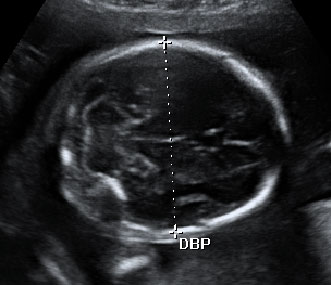

En la semana 20 de gestación el feto aún tiene mucho espacio para poder moverse. La embarazada notará esos movimientos, que se observan en la ecografía en 4D. Son las clásicas "pataditas" que nota la madre dentro del útero.